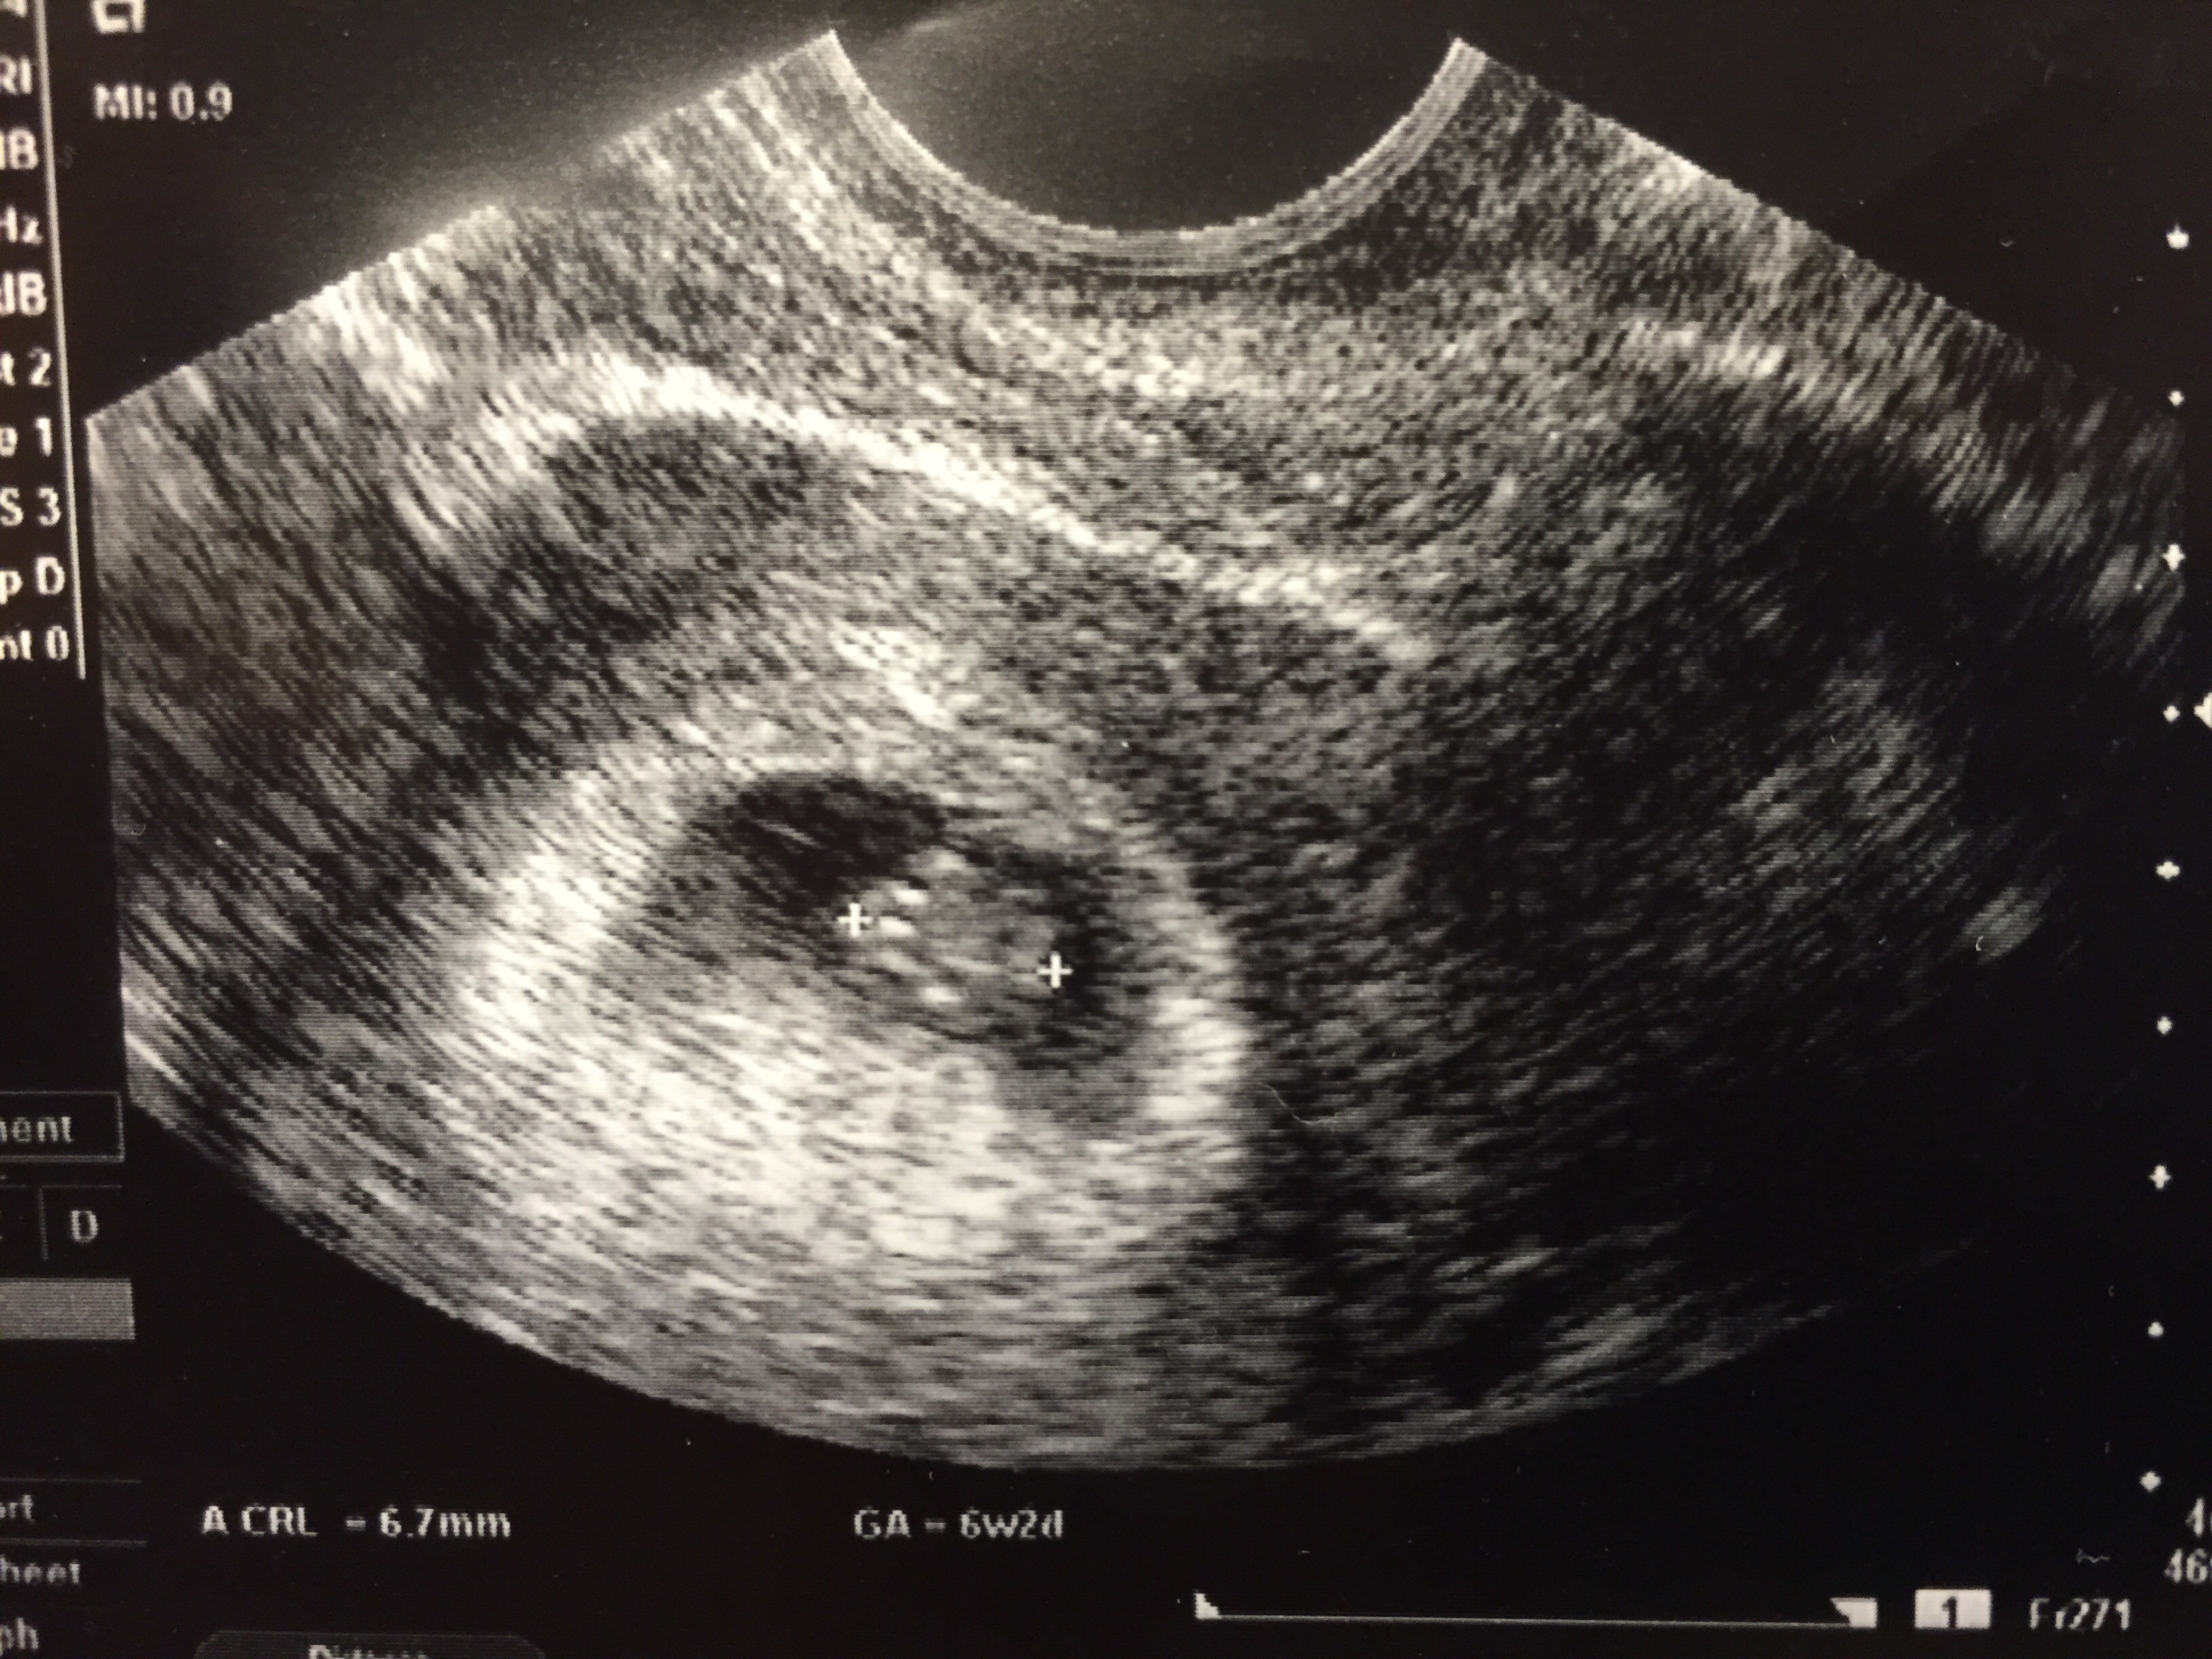

Our little one today! 6w1d

108HB